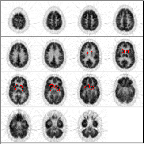

This is a normal PET scan. Abnormal PET scans will be compared with it in this tutorial about image quality control. The checklist on the right will be completed as we work through image quality control issues relating to neurological scan evaluation. This scan depicts fifteen planes (imaged simultaneously). The top of the brain begins in the upper left corner. Moving from left to right through each row, the final image is from the bottom of the brain.